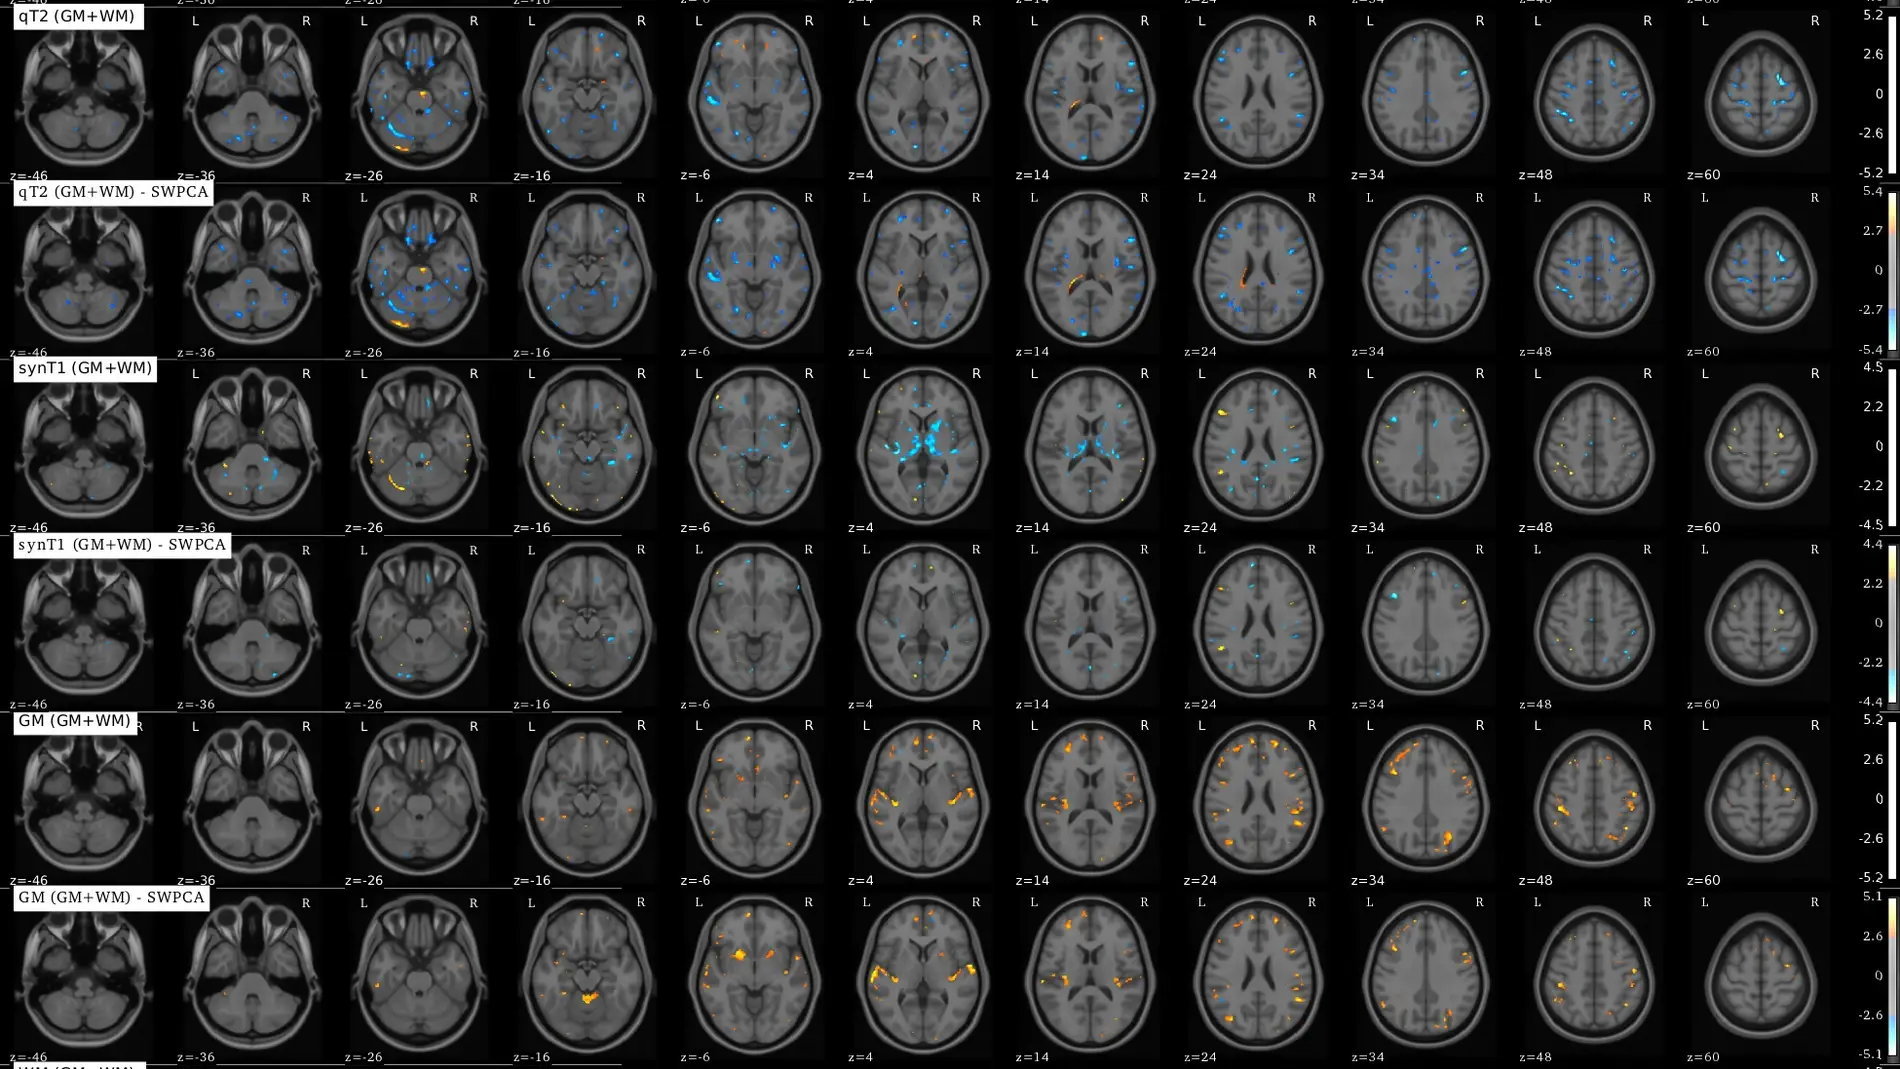

Para solucionar este problema, los investigadores han desarrollado un método estadístico llamado SWPCA (Significance Weighted Principal Component Analysis), que descompone los escáneres cerebrales como una combinación lineal de unas “componentes” que modelan las posibles fuentes de variabilidad en las imágenes cerebrales.

Después, analizaron cuáles de estas posibles fuentes eran debidas o no al trastorno o a diferencias de adquisición, y eliminaron estas últimas. De esta forma, una vez eliminada esta variabilidad, realizaron un análisis exhaustivo obteniendo resultados mucho más precisos.

Los investigadores han conseguido cancelar los efectos del lugar de adquisición en una base de datos de RM de pacientes con TEA, adquirida en varias sedes del Reino Unido, y examinar qué diferencias encontraron en esta base de datos corregida.

Tras ello, han concluido que las diferencias entre afectados y controles no eran relevantes, y que probablemente la mayoría de los estudios realizados con esta y otras bases de datos (como se ha comprobado también por otros estudios) estén afectados por este problema, donde los falsos positivos de TEA tienen como causa, en parte, diferencias entre los lugares de adquisición.